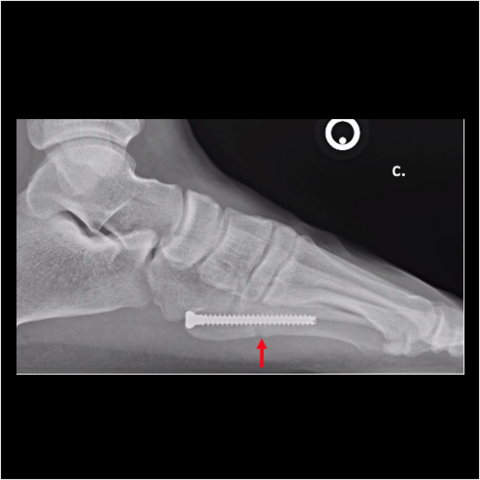

Figure 5c

Figure 5c. The 24-year-old required hardware removal and application of external fixation for gradual compression. Most cases heal within 6 weeks with gradual compression weekly.

-

Figure 5d